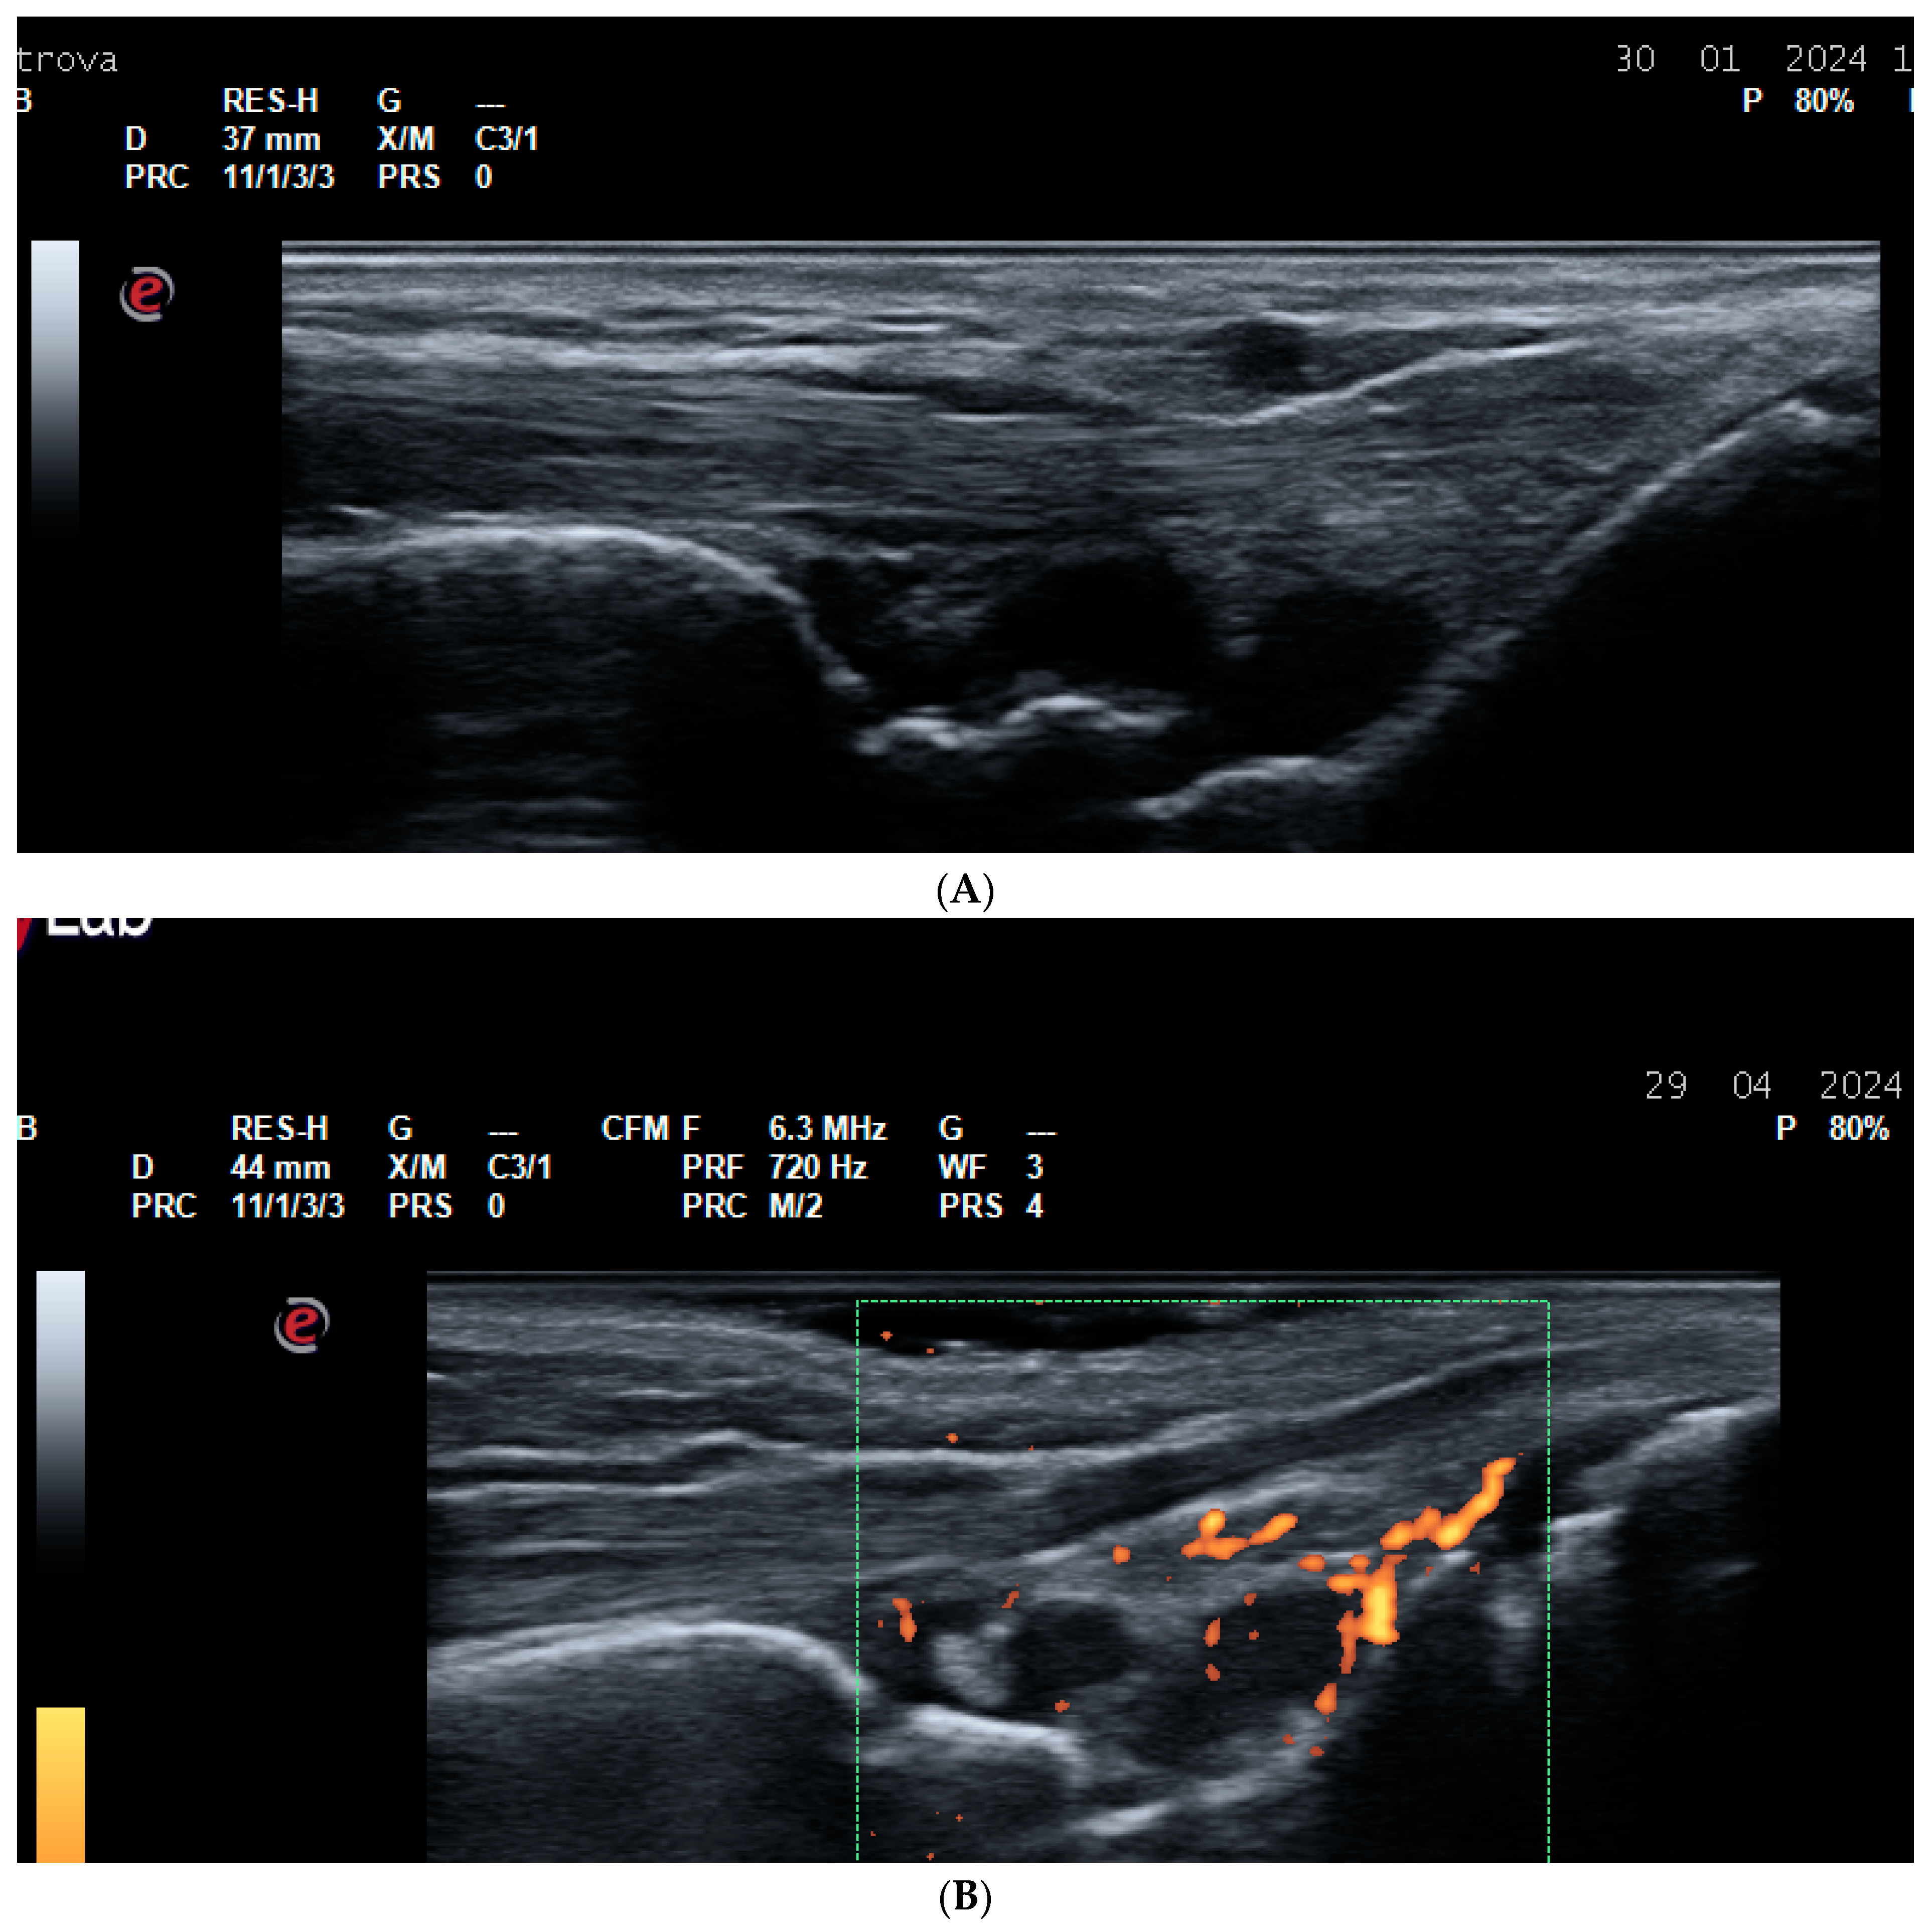

2.2. US for Assessment of Disease Activity and Monitoring Response to Therapy

- Agache, M.; Popescu, C.C.; Enache, L.; Mogoșan, C.; Filippucci, E.; Codreanu, C. Additional Value of Ultrasound in Patients with Psoriatic Arthritis within Treatment Target. J. Clin. Med. 2024, 13, 4567. [Google Scholar] [CrossRef] [PubMed] [PubMed Central]